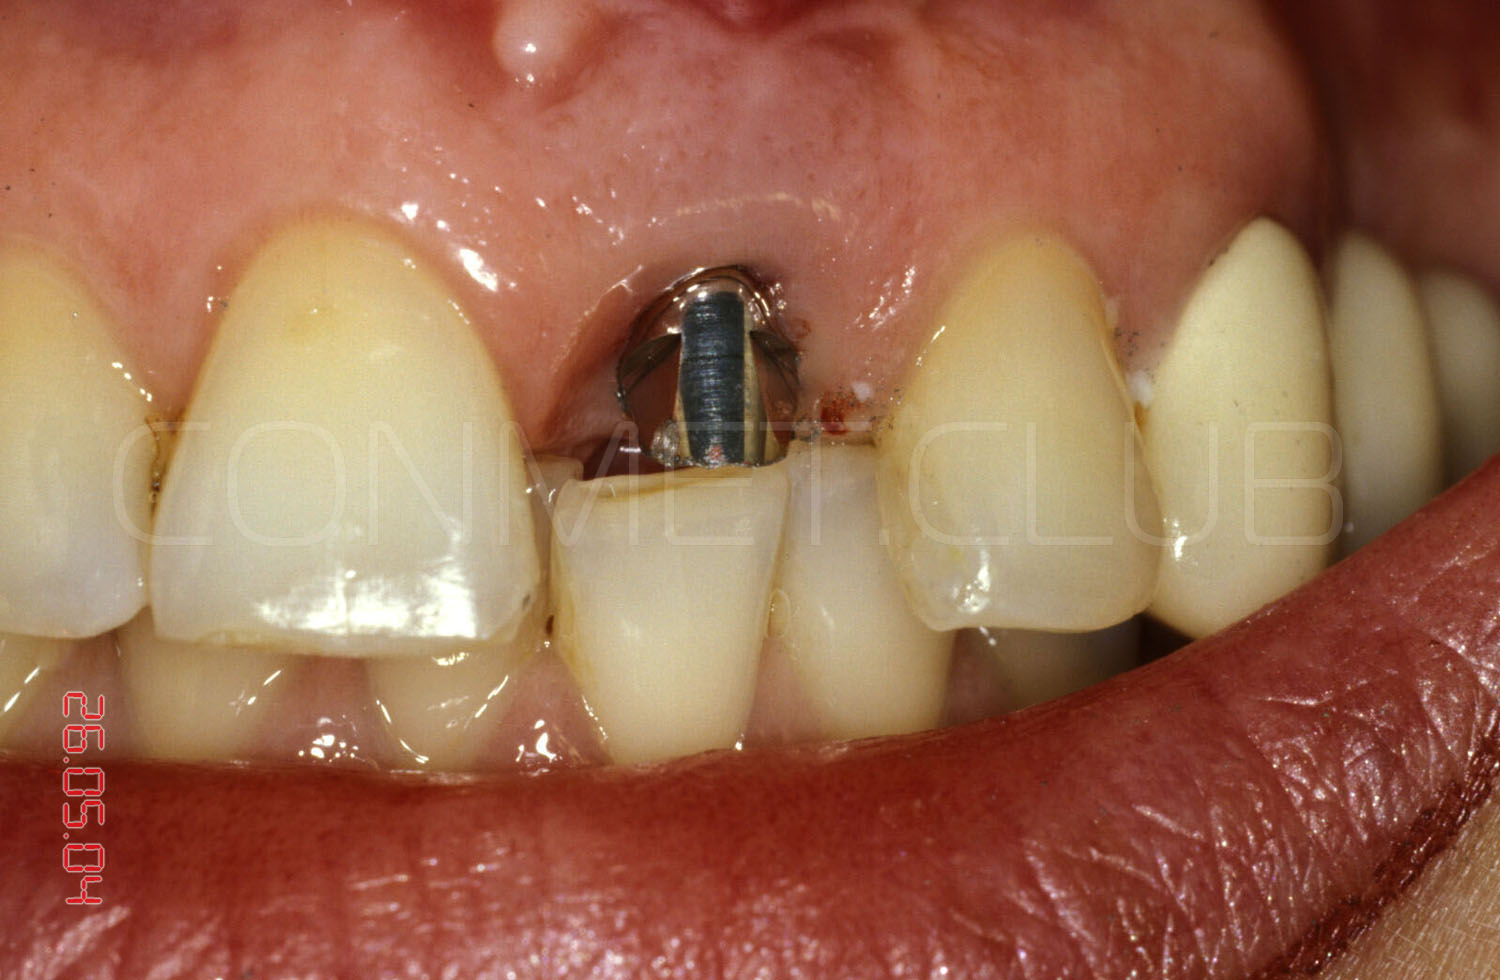

Через 3 месяца временная коронка удалена и начато изготовление стандартной металлокерамической коронки. Вид на имплантат КОНМЕТ сразу после удаления временной коронки.

Из-за глубокого резцового перекрытия пришлось сильно утачивать стандартный, прямой абатмент. Безусловно не самая простая ортопедическая ситуация с сложно прогнозируемым сроком службы.